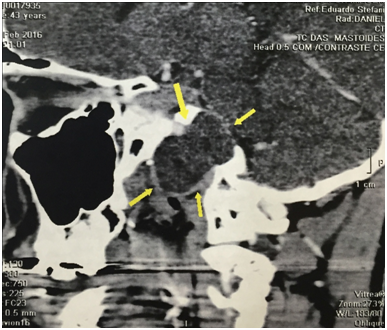

A 43years old man presented with 6month history of intermittent right hemicranial headache and ipsilateral conductive hearingloss. The patient had no historyof head trauma. The MRI demonstrated a large and expansile right petrous apex lesion hyper intense on both T1- and T2-weighted scans, without diffusion restriction or internal contrast enhancement. The CT scan showed and expansile and lyticlesion with surrounded bony erosion (Figures 1-4).

Figure 3 Preoperative sagital contrast CT Scan with a right expansile petrous apex lesion.